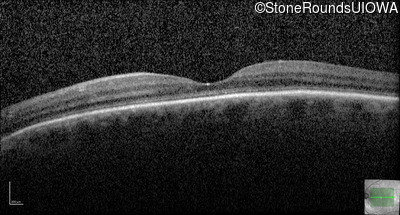

Optical Coherence Tomography - Left - 20/400 sc

Exemplar / OCT Stack

OCT Stack